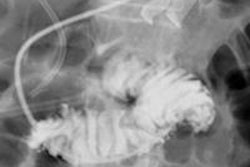

Biplane vs. single-plane imaging devices

One of the fundamental issues in the design of a hybrid OR suite is the choice for each room between biplane and single-plane imaging devices. If the projected case mix favors neuroendovascular procedures, biplane devices are desirable. However, the trade-off is a less effective setup for open procedures owing to the nature of the imaging table.

Currently, pedestal tables are not compatible with biplane devices, thus requiring surgeons to perform open techniques on an imaging table when biplanes are installed in hybrid operating rooms. On the other hand, if it is projected that only a limited number of neurological procedures will be performed in the suite (if any), a single-plane imaging device is a more appropriate selection from cost and operational efficiency standpoints.

Thanks in part to the development of faster and smaller microprocessors, the capabilities of both single and biplane devices have evolved rapidly in recent years. They now offer a host of axial imaging acquisition and postprocessing options with 3D imaging capability.4 Further, incorporation of robotics helps increase the flexibility in positioning these advanced imaging devices.

As more use of intraoperative axial imaging has become the standard of care in vascular practices, the consideration for more flexible C-arm positioning has become a critical factor in a hybrid suite. This is due to the nature of complex vascular hybrid procedures such as endovascular aneurysm repair (EVAR) and thoracic endovascular aortic/aneurysm repair (TEVAR), which may require various angles for image visualization and rotational angiography during the case.

Furthermore, having the ability to move the C-arm out of the surgical field for open cases and for a certain time during a hybrid procedure when no imaging is required enhances the intraoperative workflow and arguably patient safety. A C-arm mounted on a robotic arm with numerous pivoting joints allows for great flexibility in imaging the patient, superior axial imaging, and the ability to move the C-arm out of the way when not in use.

Given these considerations and our projected case mix, we decided that we should have two rooms each for biplane and single-plane devices: the biplane units primarily for the neuro work and the single-plane unit for abdominal, peripheral, EVAR, and TEVAR procedures.